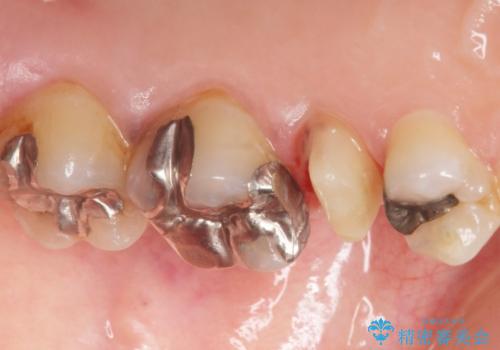

歯ぐきを押すと痛い 神経が死んでいる歯の治療 40代女性

- 歯の根のあたりの歯ぐきを押すと痛むことを主訴に来院された患者様です。

精査したところ、左上の小臼歯(左上5)の神経が死んでいました。

根管治療後、セラミッククラウンによる補綴を行いました。